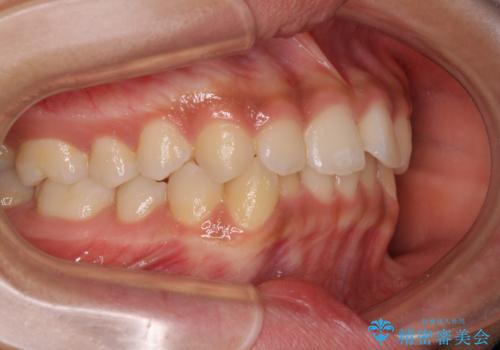

前歯のデコボコを治したい インビザライン・モデレートによる矯正治療

- 上下前歯の叢生を気にして来院された患者様です。

インビザラインでの治療を希望されていて、デコボコの程度が中等度であり、安価なパッケージにて対応可能と判断されたため、インビザライン・モデレートを用いて矯正治療を行うこととしました。